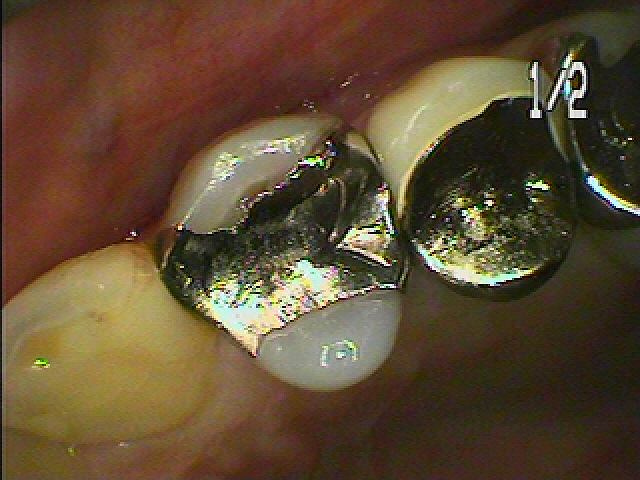

問題の歯になります

中は黒く虫歯にもなってきていました